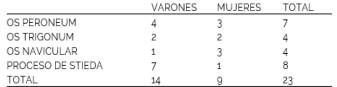

El grupo de pacientes con alguna de las variantes descritas se conformo por 14 varones y 9 mujeres. La distribución de hallazgos en relación al sexo se manifestó de un modo equitativo en la mayoría de las variantes, sin embargo la presencia del PS fue 87.5% predominante en pacientes varones. (Tabla 2).